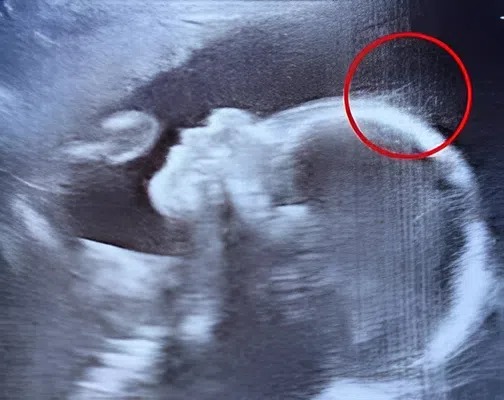

A little girl complains of abdominal pain after a weekend at her stepfather’s

After a weekend at her stepfather’s, a young girl complains of stomach ache. The doctor looks at the ultrasound and promptly calls for emergency help… It should…